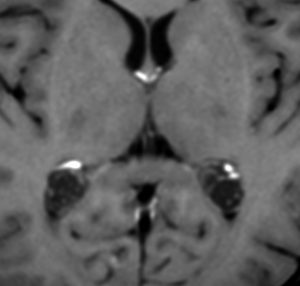

1歳児の巨大な脈絡叢乳頭腫です。このくらいのサイズになると手術で出血死することもあります。右側の画像は手術後のMRIで幸い全摘出できています。乳幼児のこのように巨大なものでは無理して全摘出にいどまないで,シャントをして水頭症を改善して,化学療法で腫瘍を小さくしてから,開頭手術するという方法もあるでしょう。執刀医の経験値で判断は異なります。